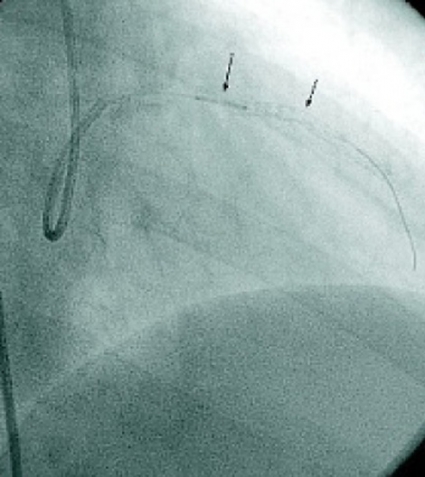

Den största utvecklingen kommer sannolikt att ske i behandlingen av hjärtinfarkt med ST-förhöjning, där den mortalitetsreducerande effekten av PCI, jämfört med trombolys, inte står i proportion till frekvensen av öppet kärl. De sannolika orsakerna till detta torde vara att man i samband med att man öppnar kärlet inte bara får en distal embolisering utan även en större reperfusionsskada än med den mer gradvis verkande trombolysbehandlingen. Idag används olika typer av intrakoronara katetrar som gör det möjligt att suga upp tromber. Dessa katetrar är med få undantag [19] dåligt dokumenterade i fråga om både effekt och eventuella komplikationer. Vår erfarenhet är att det kan förekomma en risk för stroke i samband med »koronarsugning«, då katetern dras ut i aorta med en eventuell tromb distalt som kan lossna. Det finns således ett stort behov av randomiserade studier inom detta område. Vidare har konceptet att reperfusionsskada kan förhindras med läkemedel inte testats nämnvärt på människa. Kateterburna interventioner i samband med hjärtinfarkt med ST-förhöjning gör det möjligt att testa detta koncept, då man via ballongkatetern kan infundera läkemedel innan man öppnar kärlet.